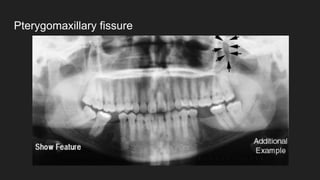

● Pterygomaxillary fissure

Pterygomaxillary fissure